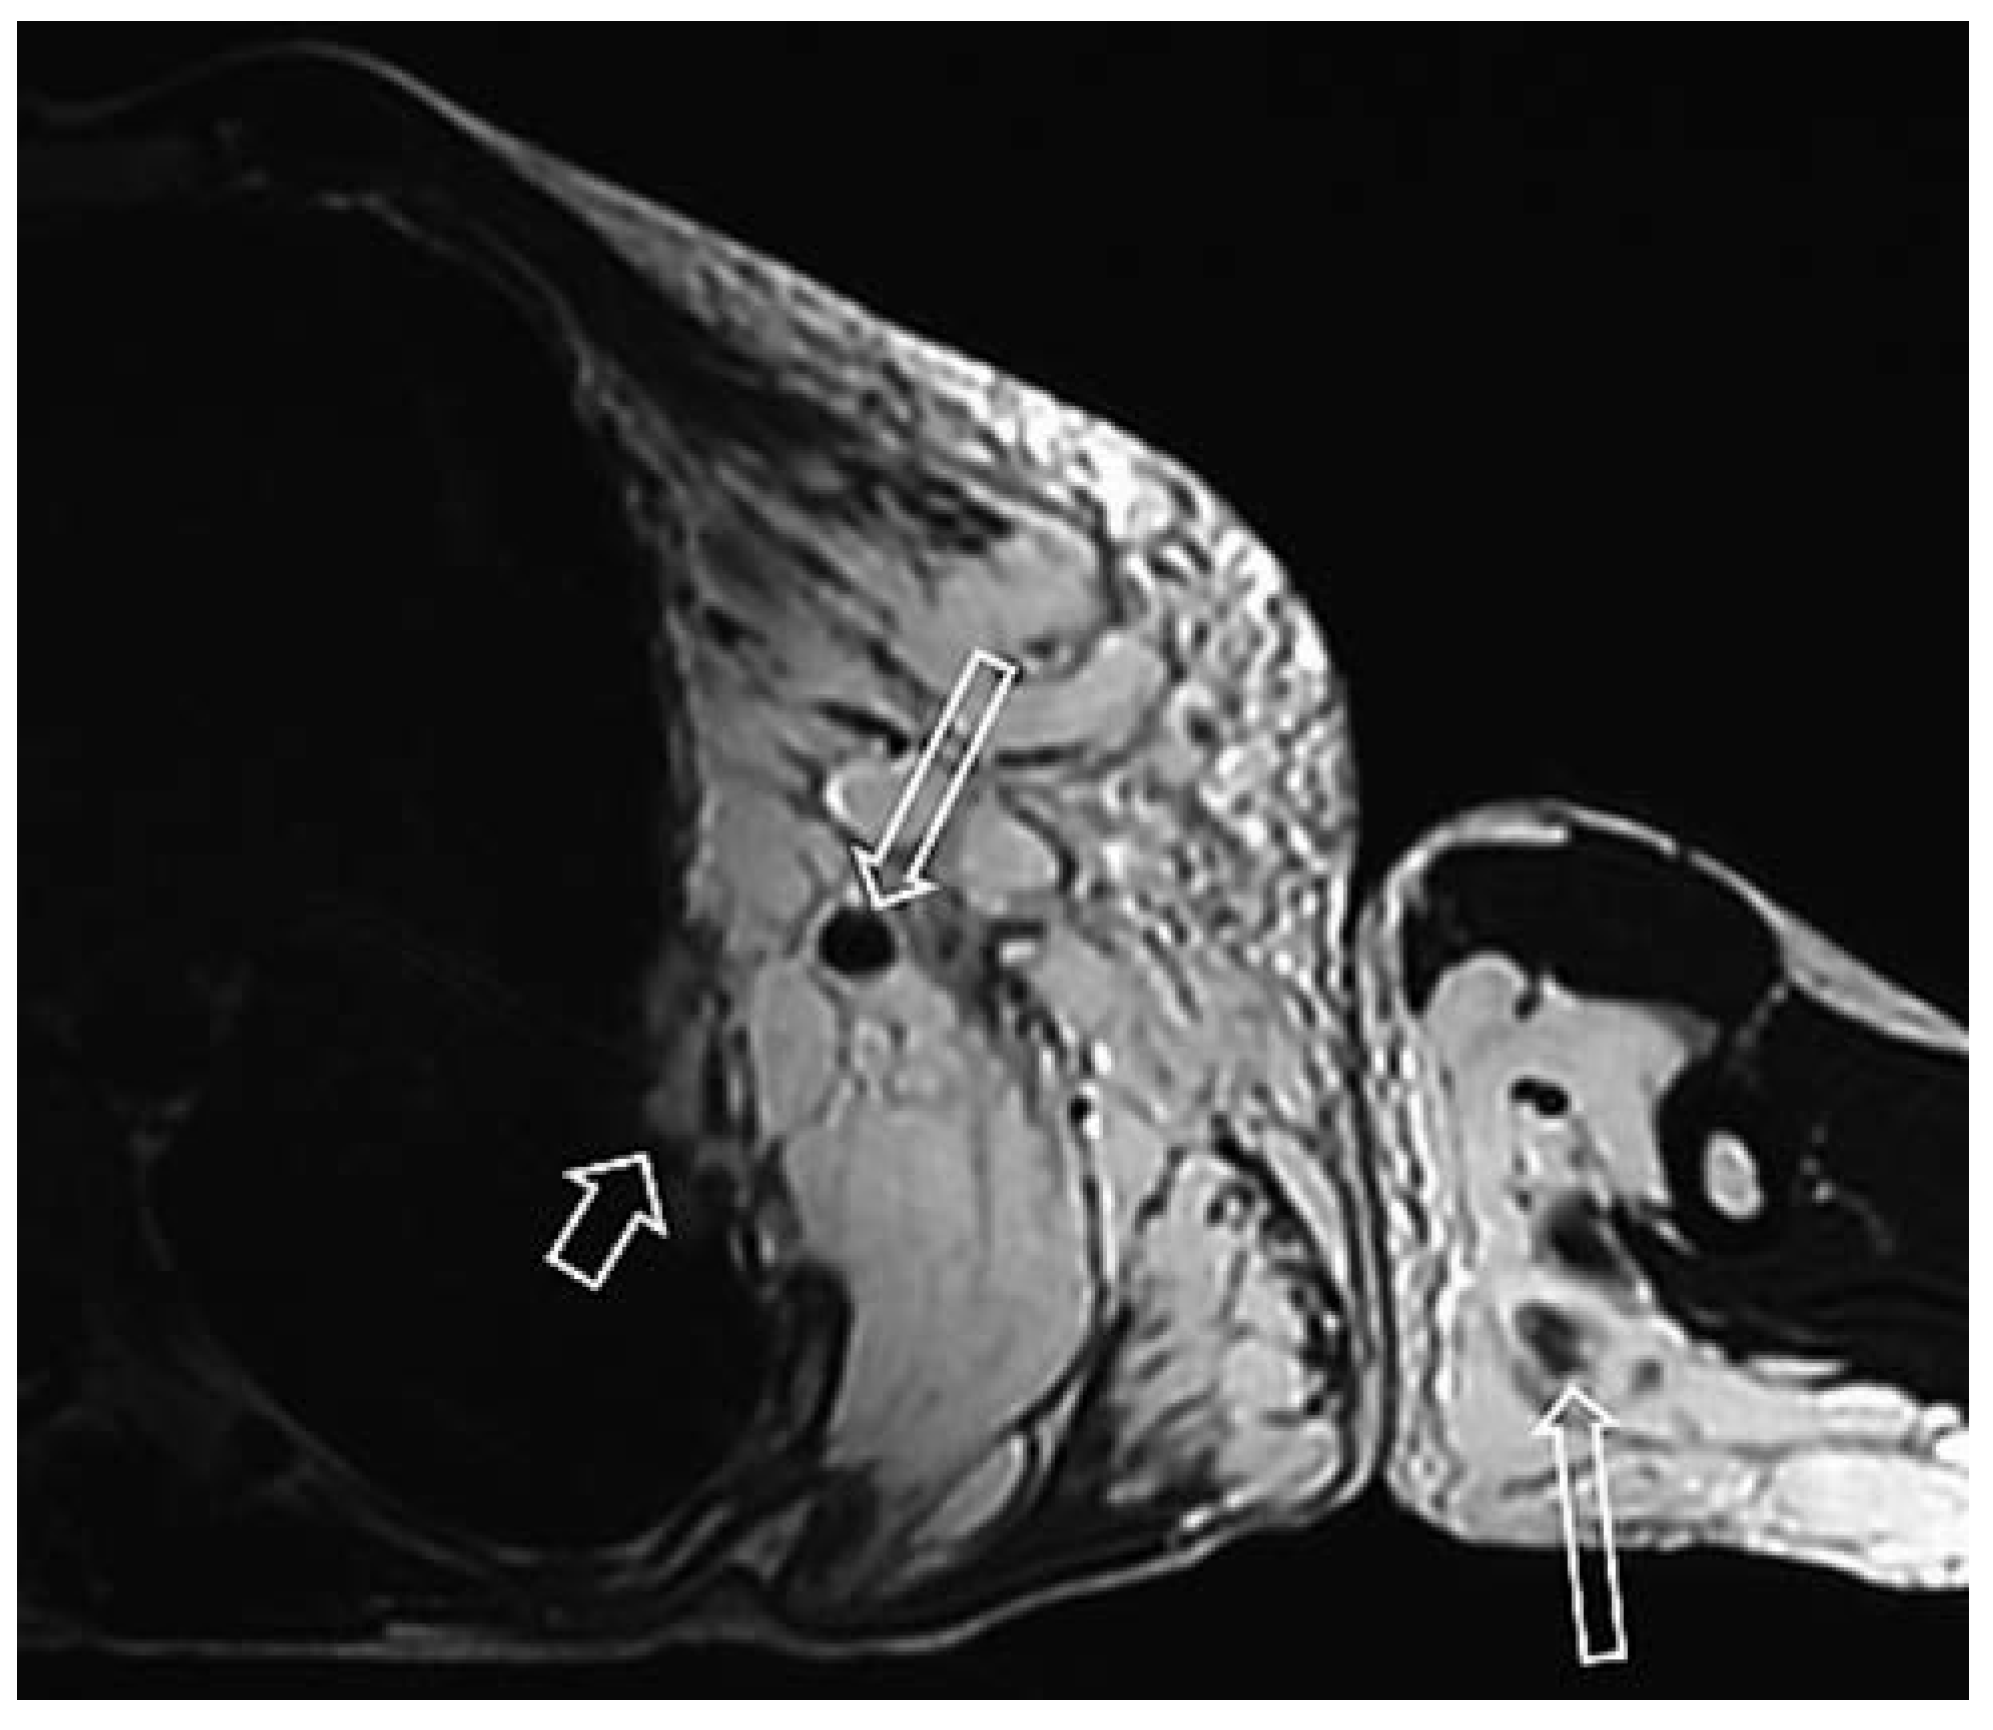

Venöse Malformationen

Lymphatische Malformation

- Jans, L.; et al. MRI demonstrates the extension of juxta-articular venous malformation of the knee and correlates with joint changes. Eur Radiol. 2010, 20, 1792–1798. [Google Scholar] [CrossRef]